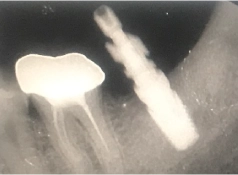

• Tình trạng răng trước đây:Mất răng số R37

• Bác sĩ chỉ định:Cấy ghép 1 trụ Implant

• Implant sử dụng:Implant Mis C1 Đức

• Răng sứ sử dụng:Răng sứ Zirconia Đức

Cảm nhận được sự gần gũi và trình độ chuyên môn tốt của bác sĩ Thanh Phong, nên anh Tiến đã tự tin, sẵn sàng tiến hành trồng răng Implant, khôi phục lại hàm răng chắc khỏe. Kết quả nhận được cũng đúng như mong muốn của anh. Trụ Implant tích hợp thành công vào xương hàm, thay thế cho chân răng thật một cách vững chắc và giúp anh ăn uống thoải mái hơn rất nhiều.

Sau nửa năm trồng răng quay lại tái khám, anh Tiến chia sẻ thêm những cảm nhận về chiếc răng mới của mình: “Trong quá trình ăn nhai anh không biết cái nào là răng giả luôn, vì ăn uống rất là tốt, không có lỏng lẻo, xộc xệch gì hết. Anh ăn được nhiều món mà trước đây không dám thử bởi vì mất răng”.